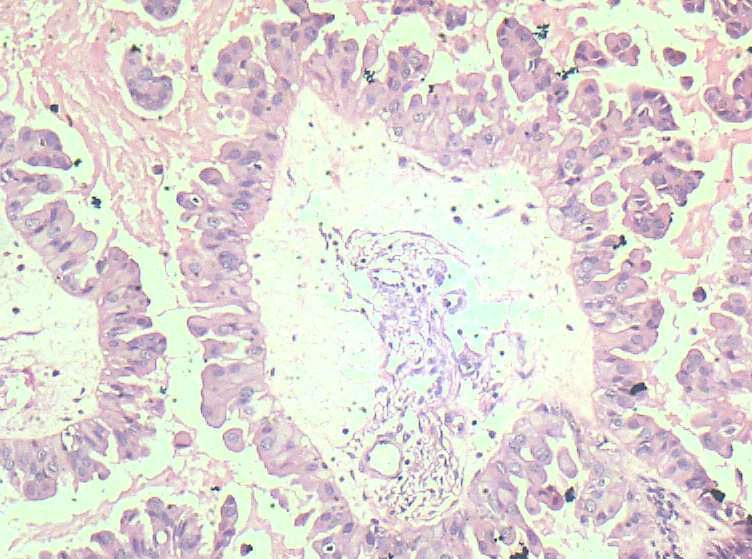

女,27岁,剖宫产术中见一侧卵巢一肿物。大体:椭圆形肿物大小3*2*1.5表面光滑,剖开内容为浅黄色胶状物,质均,囊内壁较光滑,部分见细小乳结构。

可见增生的上皮,形成乳头或微乳头,见到钉突和出芽式的生长,漂浮的上皮细胞簇,细胞核轻-中度不典型增生。

从所给的图片来看,发交界性浆液性乳头状囊腺瘤,仔细找找是否有微浸润的存在,再排除浸润成为癌的可能性。

浆液性乳头状瘤是可以确定的。

是否是交界性?图片中乳头分支复杂,细胞确实有异型性。但是不知道在妊娠期,激素水平和平时不同,这时的标准怎么掌握?请高手指教。